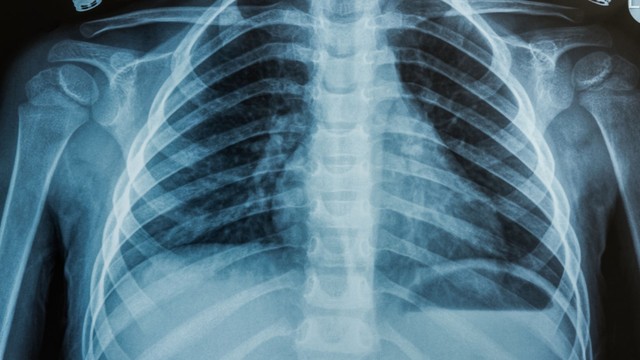

X quang